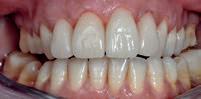

Trata-se de uma paciente com 37 anos que pretendia melhorar a estética dos seus dentes. Já havia sido tratada com restaurações diretas, mas o resultado foi sempre insatisfatório (Fig. 1).

Figura 1

Na análise do sorriso apresentava os seguintes problemas: 1. Dentes superiores escuros e com manchas, principalmente o dente 21. 2. Restaurações em compósito com cárie subjacente, com infiltração marginal e discromia. 3. Curvatura da linha incisal invertida 4. Arcada em forma de “V” numa vista oclusal 5. Corredores vestibulares pouco preenchidos 6. Mordida cruzada de todos os dentes do 2º quadrante 7. Festonado gengival desalinhado (11, 21, 22 e 23 elevados)